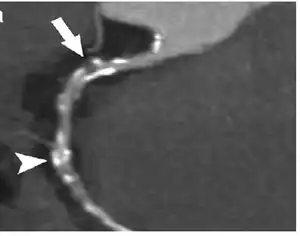

Coronary computed tomography angiography (CCTA)

Computed tomography angiography (CTA) is an imaging methodology using a ring-shaped machine with an X-ray source spinning around the circular path so as to bathe the inner circle with a uniform and known X-ray density. Cardiology uses are growing with the incredible developments in CT technology. Currently, multidetector CT, specially the 64 detector-CT are allowing to make cardiac studies in just a few seconds (less than 10 seconds, depending on the equipment and protocol used). These images are reconstructed using algorithms and software.